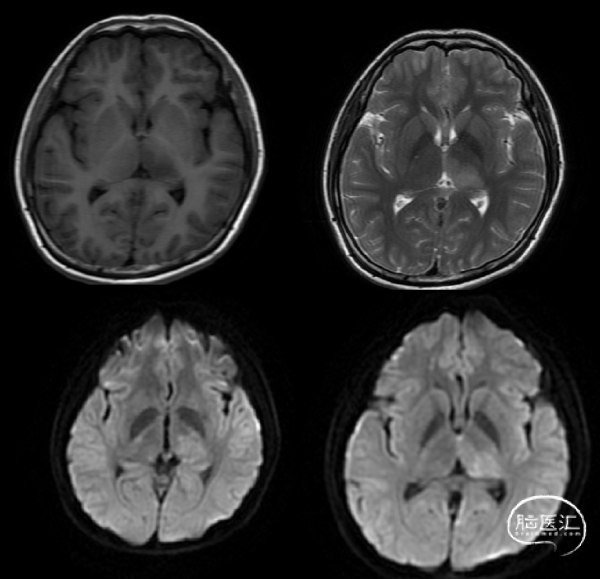

术前影像学资料

患者入院急诊完善MRV提示:左侧横窦、乙状窦、直窦血流信号充盈缺损,考虑静脉窦血栓形成(图二)。

术后1月患者随访MRV:MRV可见右侧横窦、乙状窦可见血流信号,较前好转。